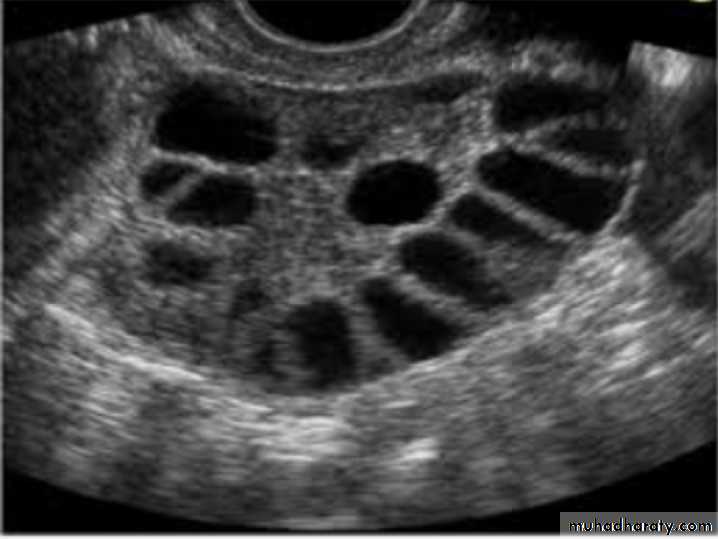

Dx: multilocular ovarian cyst

Risk: malignancy